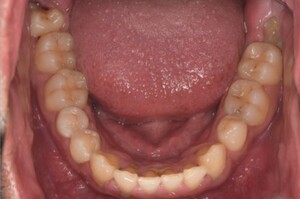

来院2回目、TBI後

症例

SRP後

初診時、TBI前

基本情報

年齢・性別 27歳・男性

主訴 主訴:左右下の歯ぐきに違和感がある

治療部位:全顎

治療内容 1.歯周基本検査、レントゲン撮影、口腔内写真、歯磨き指導、歯石除去、着色除去

2.SRP(スケーリングルートプレーニング)、再評価

その他

担当者所見 全体的に歯と歯ぐきの境目に歯垢(細菌の塊)が残り、日々のホームケアで落とし切れていなかったことと、歯科医院への定期検診の習慣がなかったことから、全顎的な歯肉炎になってしまったと考えられる。

歯周基本治療とホームケアで歯ぐきの腫れや歯周ポケット、出血率などかなり改善されたが、出血がまだ0%ではない為、引き続き歯ブラシの当て方をお伝えしつつ今後は定期検診で3ヶ月おきに再発しないよう一緒に管理していく。